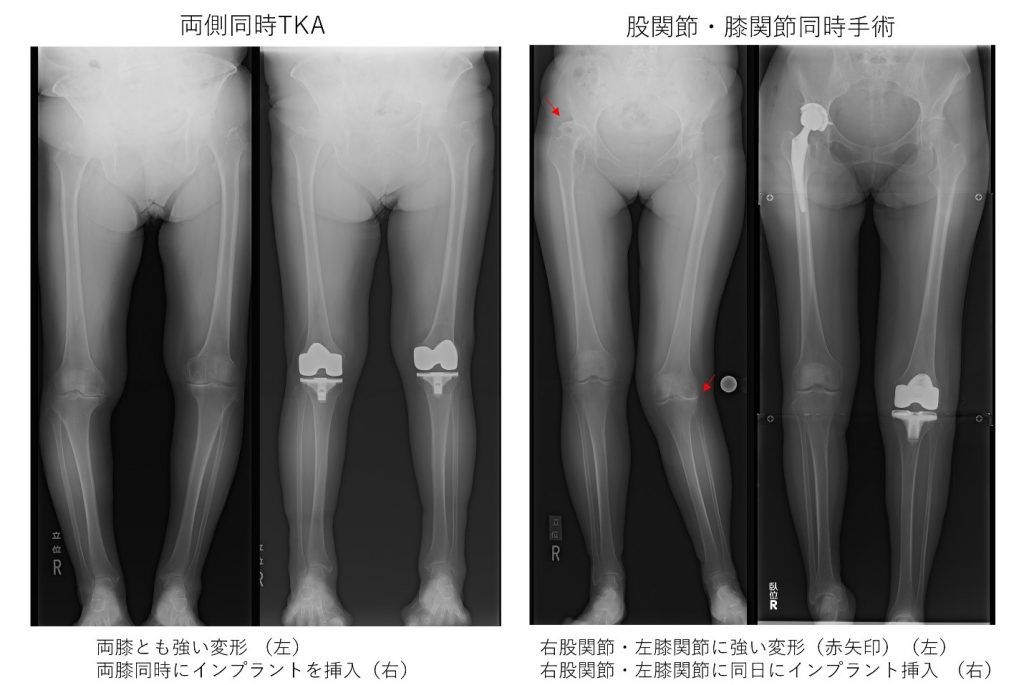

医師は X 線 (X 線撮影) を使用して、骨の変化と膝関節の位置を観察します。これは変形性関節症の診断に役立ちます。

多くの場合、変形性膝関節症の第一選択の画像検査は X 線です。 整形外科医または骨の医師は、変形性関節症の兆候や症状を最初に検査した後、変形性関節症を診断するために X 線写真を撮るよう紹介する場合があります。

X線では軟骨の画像を撮影することはできません。ただし、骨の間の空間が狭くなることによる軟骨の喪失が明らかになる場合があります。これは、変形性関節症や軟骨が侵食されたその他の関節疾患の最も明白な症状です。医師が骨や軟組織をさらに詳しく観察したい場合は、MRI 検査を紹介することもあります。

医師が変形性膝関節症と診断した場合、医師は次の基準に基づいて重症度グレード 0 ~ 4 に基づいて画像にラベルを付けます。